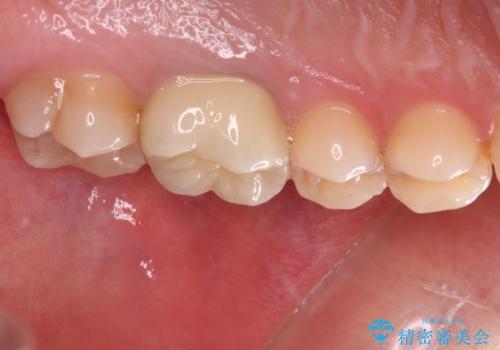

適合の良いセラミック治療は、むし歯再発のリスクが低いです。

目立つ銀歯がなくなり、患者様は大変満足されました。